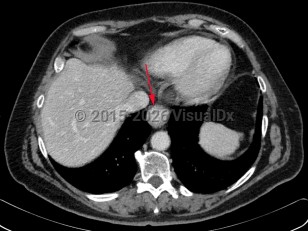

Aortic dissectionAortic dissection

Penetrating atherosclerotic ulcer

Aortic intramural hematoma